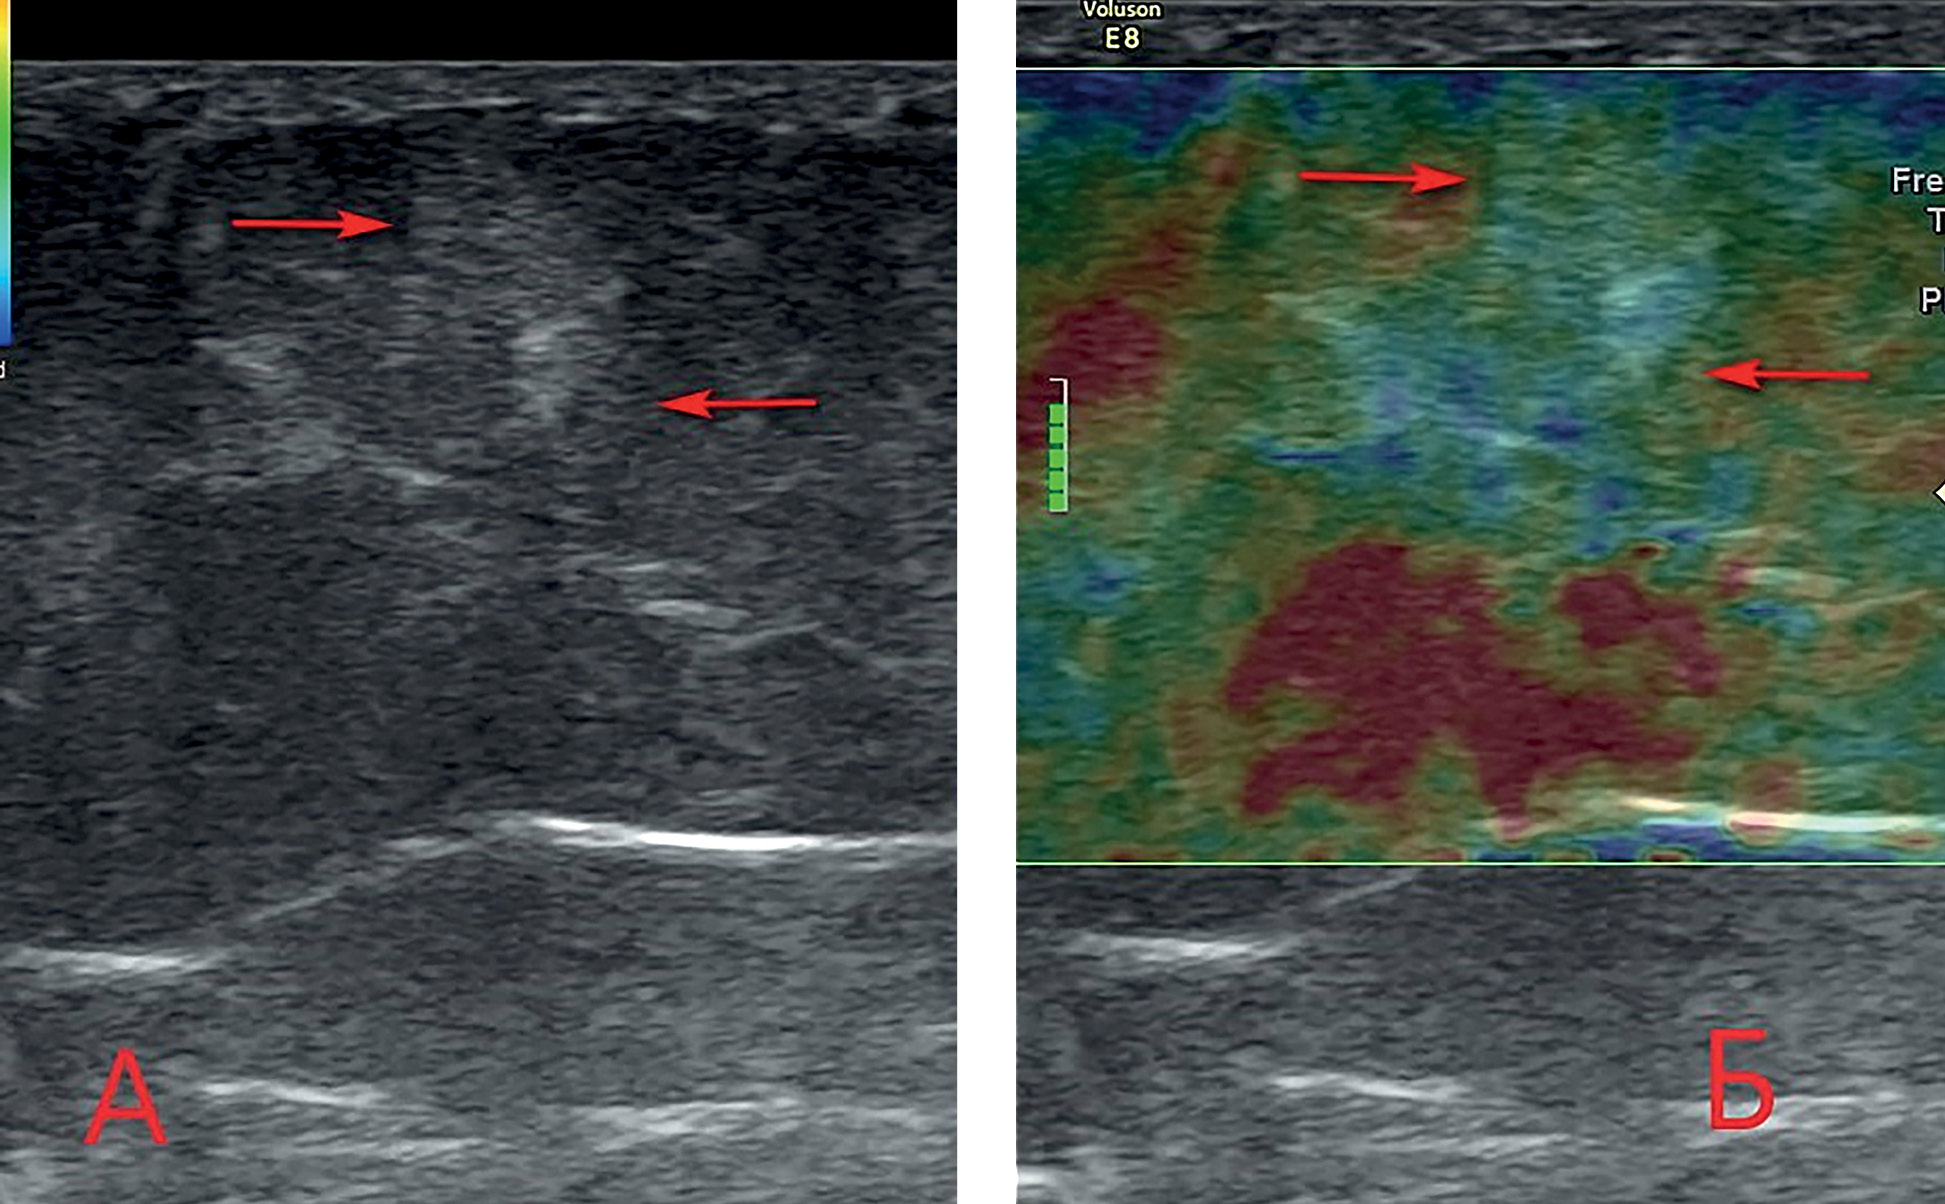

5. Fig. 5. A heterogeneous site of increased rigidity lipohypertrophy in the subcutaneous fatty tissue of the anterior abdominal wall in the area of insulin injection. A - gray-scale scan in B-mode; B - real-time compression sonoelastography: areas of increased stiffness are colored blue. Boy B., 48 years old, type 2 diabetes mellitus, insulin analogue therapy (levemir) for 6 months. | |

(379KB)